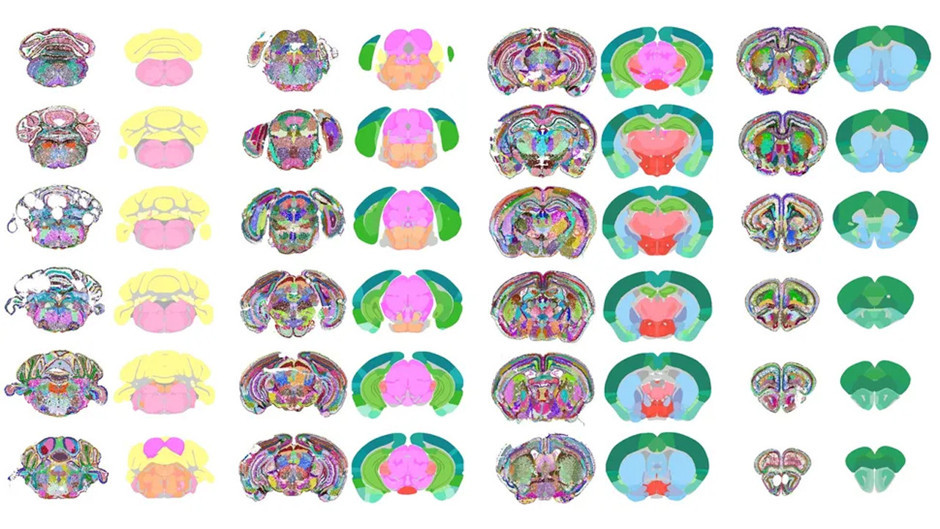

Sistem, fare beyninden elde edilen ve her hücredeki yüzlerce genin etkinliğini içeren karmaşık verileri analiz ederek, beynin farklı bölgelerindeki hücrelerin birbirine göre konumlarını değerlendirdi. CellTransformer, bu analizle verileri dönüştürerek eksik kalan bağlantıları tamamladı ve sonuçta insan eliyle yapılan etiketlemelerden çok daha net ve keskin beyin haritaları üretti. Hatta AI, daha önce bilimsel kayıtlara geçmemiş, çok ince yapılı yeni bölgeleri bile tanımlamayı başardı.

Yeni harita, yaklaşık 9 milyon hücreye karşılık gelen 1.300 farklı beyin bölümünü kapsıyor. AI tarafından üretilen bu harita, Allen Institute’un daha önce büyük emekle oluşturduğu yüksek çözünürlüklü haritayla karşılaştırıldı ve büyük oranda uyumlu olduğu görüldü.

CellTransformer, hafıza işlevlerinde kritik rol oynayan hipokampus gibi bilinen bölgeleri başarıyla haritalandırmanın yanı sıra, duyusal bilgileri işleyen ve uyku düzenlemesinde görev alan orta beyin retiküler çekirdeği gibi ulaşılması zor ve karmaşık bölgeleri de yüksek doğrulukla belirleyebildi.